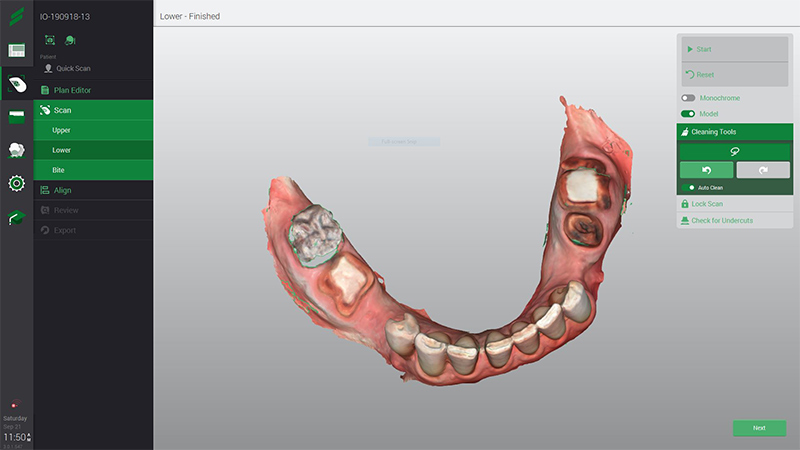

Une empreinte numérique avec la caméra VirtuoVivo (Dentals Wings) est réalisée et l’étude préimplantaire sera réalisée simultanément à la planification.

Fig. 38 : empreinte numérique réalisée avec la caméra VirtuoVivo.

Nous retrouvons maintenant comme précédemment les différentes vues du cas n°2 : l’os (en vert) et les dents segmentées (en rouge) et le rendu surfacique de l’arcade à l’état initial (en beige). À noter que bien que l’empreinte soit en couleur au format ply (fig. 38), les prothésistes convertissent le fichier en monochrome.